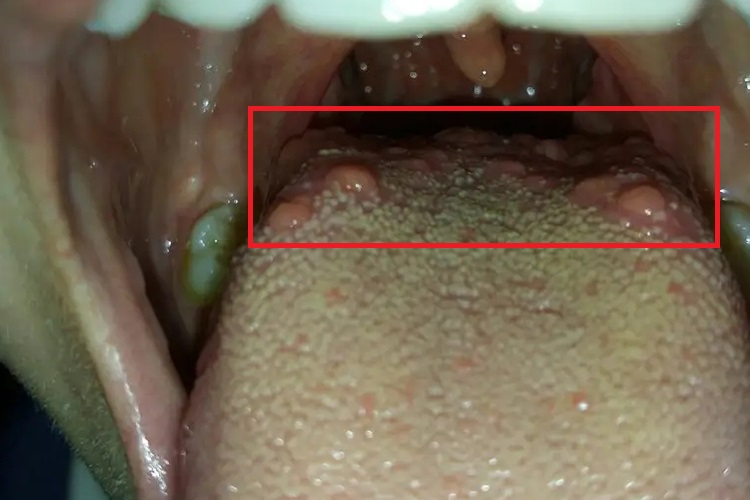

舌背部舌乳头突起常见于舌乳头炎,疾病具有多种分型,其中菌状乳头炎、轮廓乳头炎和叶状乳头炎的病变表现可有乳头突起。

菌状乳头炎:发生炎症时乳头肿胀、充血、灼热、疼痛不适感。如果菌状乳头肿胀明显,上皮薄而呈深红色,舌背前部形似草莓,称为草莓舌或杨梅舌。

轮廓乳头炎:存在炎症时乳头肿大突起,轮廓清晰、发红。疼痛感不明显,少数患者有味觉迟钝。也有患者无意间发现,并将其误认为肿瘤而感到恐惧。

叶状乳头炎:炎症时乳头红肿,乳头间皱褶更显凹陷,患者常有明显的刺激痛或不适感,常因担心其会发展为肿瘤而导致不适感加重。